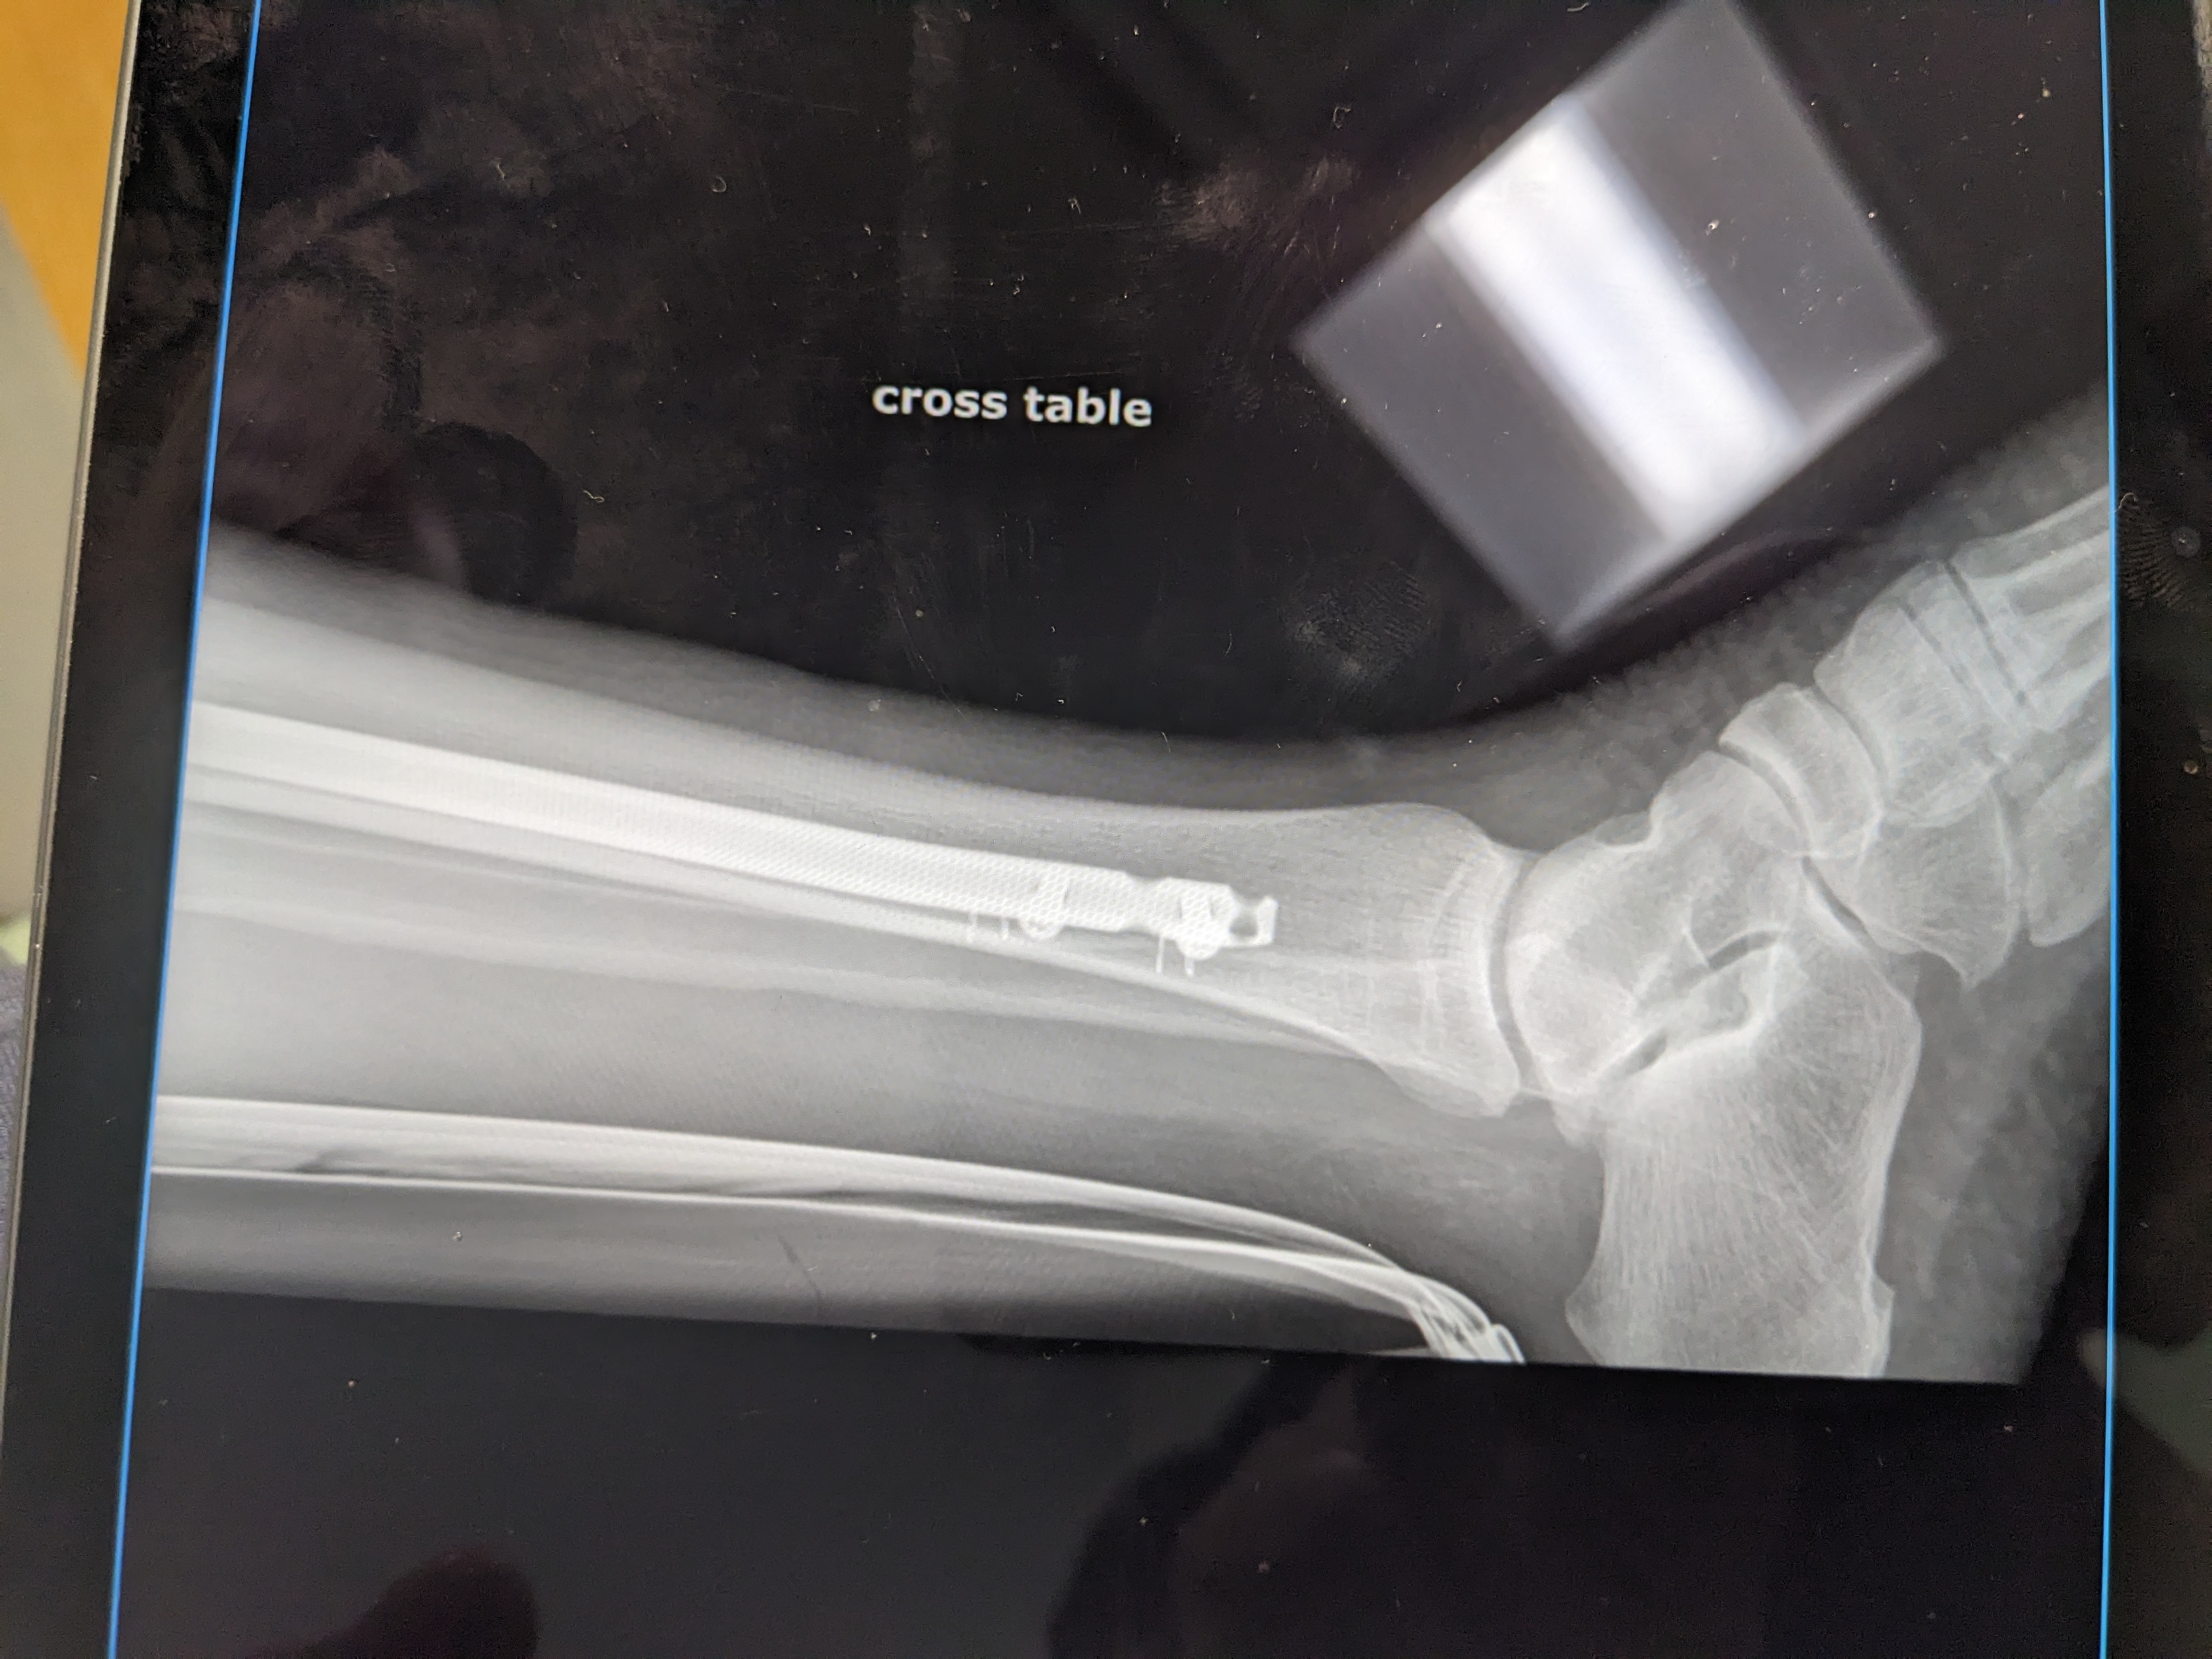

Calf was crushed. Multiple compound fractures bone piercing the bloody flesh.

My platoon of guardian angels prevented my knee and ankle from being destroyed, thus the surgical team was able to install at least a 1/2 pound of titanium to reconstruct what was left of my calf, as there was enough bone left to attach the titanium bones to the joints. I have nerve damage.

I underwent a third operation on my poorly healing bones. Hopefully this much hardware will allow what bones remaining to fuse. My leg is now more stable but traumatized after being opened up again.

Wow. Looks like an Ace Hardware store.

Wow that is a lot of hardware in a small space. Sure hope your recovery continues well and you can get back on your tractor.

New hardware is providing more stability. Now only hope the crunched Tibia begins to mend.